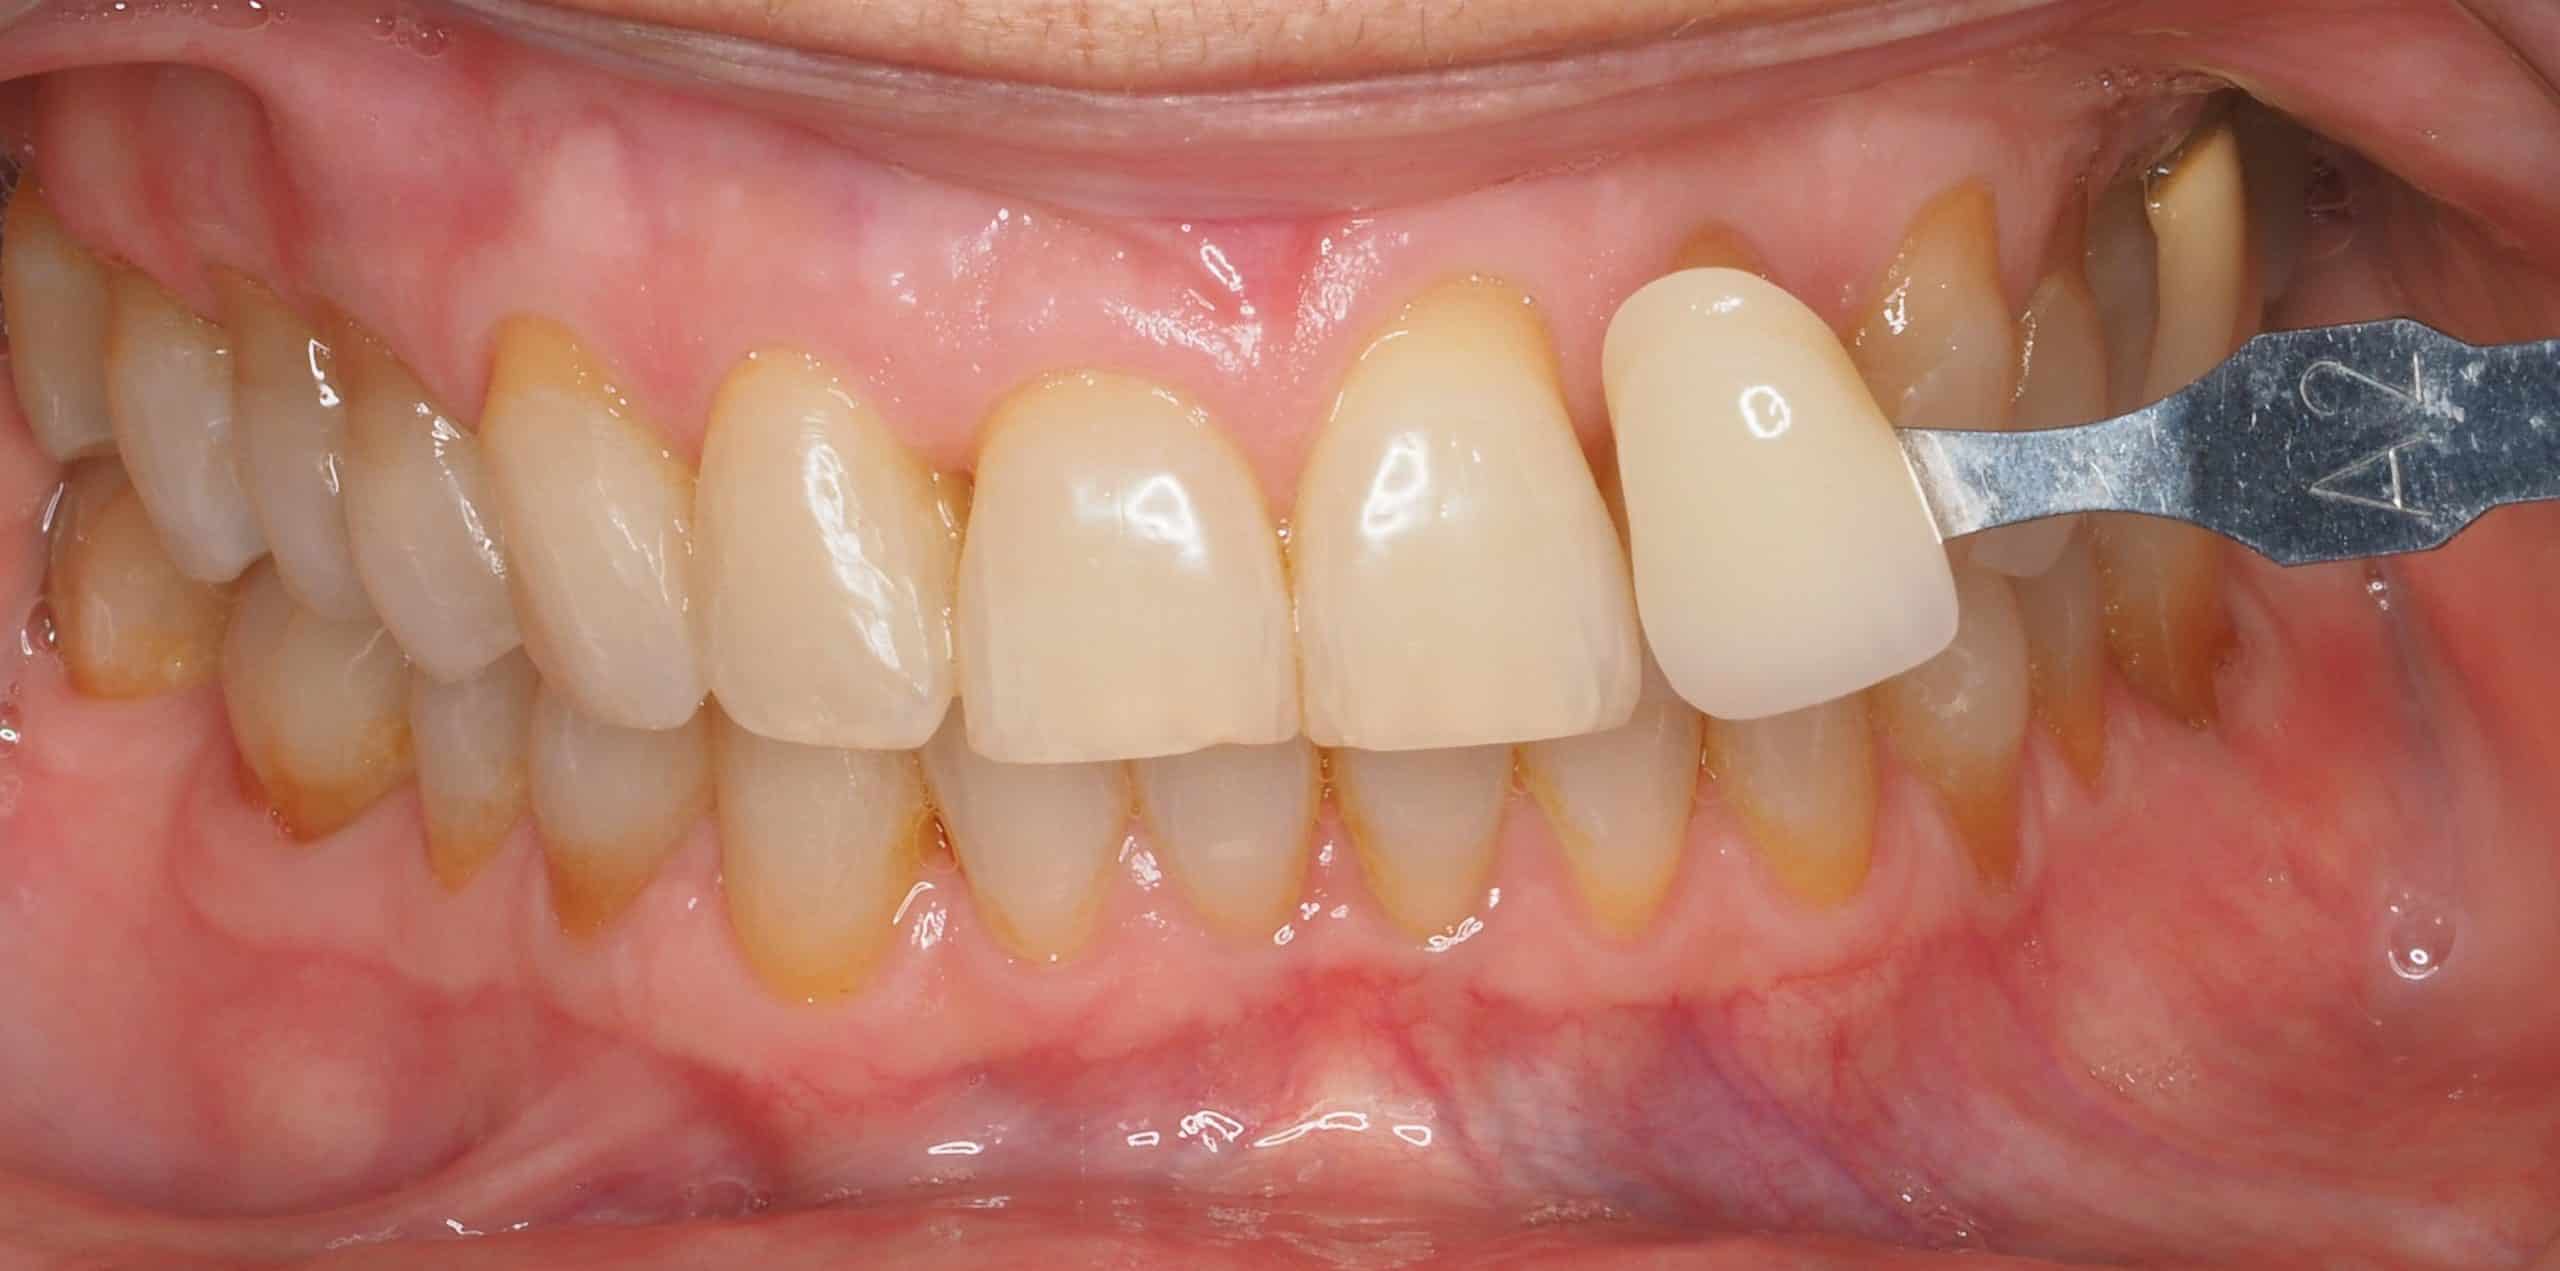

Caso 3

Rehabilitación con cerámica feldespática de dientes con tinción por tetraciclinas y malposición.